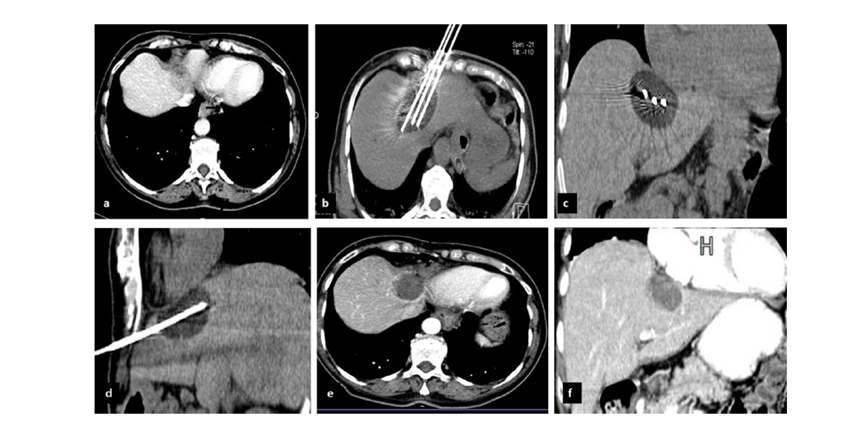

冷冻消融胆囊附近肿瘤病灶

(A)动脉期 MRI 显示胆囊附近有外周增强病变(箭头)。

(B)手术过程中 CT 显示冷冻探针位于病灶内。

(C)消融后,术后 1 个月CT 显示完全消融(箭头)。

(A)动脉期CT图像显示有一个包膜下结节(箭头)。(C) 在手术过程中的CT显示一个冷冻探针位于病灶内。随访时间中位数为7个月(范围:3-12个月),随访期间患者无局部肿瘤进展或死亡。

(A)门静脉期 CT 图像显示胆囊附近有病变(箭头)。(D)消融手术后 1 个月CT 显示完全消融。

CT引导的冷冻消融